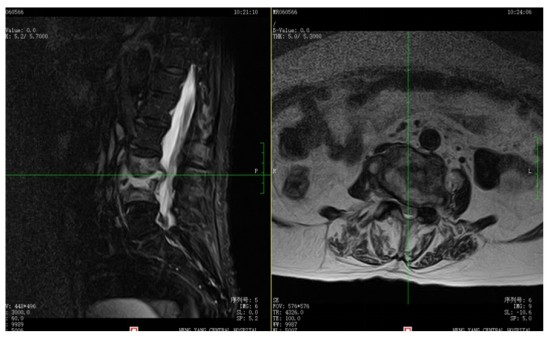

為解決老人病痛,脊柱外科錢軍博士團隊對其進行了詳細(xì)的查體以及全面細(xì)致的評估,診斷為L3、4脊柱結(jié)核伴病理性骨折、椎旁膿腫,患者腰部疼痛癥狀逐漸加重,病灶已經(jīng)壓迫神經(jīng)引起了截癱。

脊柱結(jié)核手術(shù)治療的目的在于徹底清除病灶,讓脊髓和馬尾神經(jīng)充分減壓,矯正脊柱畸形,重建脊柱的穩(wěn)定性。但李奶奶年事已高,基礎(chǔ)疾病多,手術(shù)風(fēng)險大,且脊柱特殊的解剖結(jié)構(gòu)以及復(fù)雜的手術(shù)操作,操作難度高。錢軍博士帶領(lǐng)團隊經(jīng)討論后,經(jīng)過兩周的抗結(jié)核治療,邀請麻醉科、心內(nèi)科、呼吸內(nèi)科、藥劑科、ICU等多個學(xué)科的專家開展MDT會診。